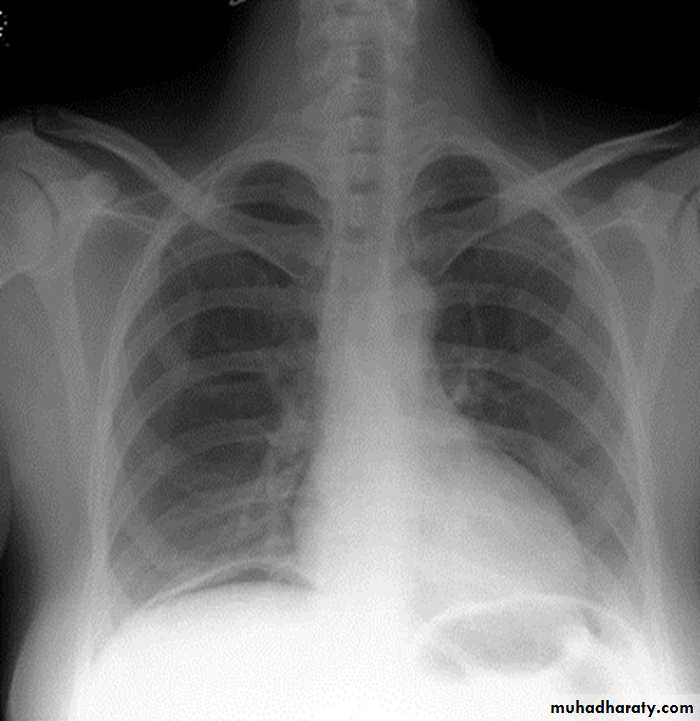

Slide11A young female sustained RTA1- What does this sign called?2- What is the underling problem?